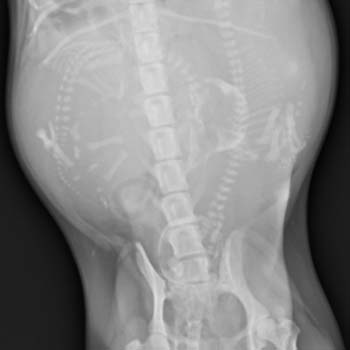

上圖為母犬出現用力生產的跡象,並且於出現羊水破裂1小時後,仍然沒有胎兒生出,因此於103年10月的夜間前往動物醫院就診。

出現水球 (胎兒的尿囊,正常生產會連同胎兒出生),但是依然沒有胎兒生出。

經過檢查後診斷為難產,原因是母狗產道狹窄,導致胎兒頭顱無法通過。主人當機立斷請獸醫師進行剖腹產,搶救胎兒的生命。